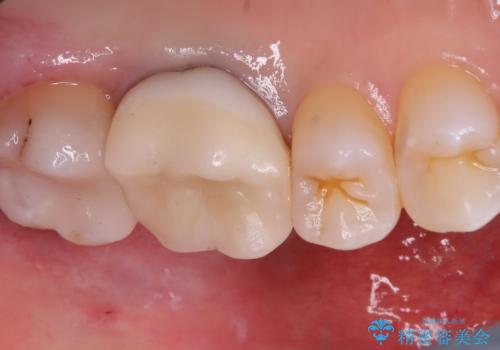

審美性、適合性の観点からセラミックインレーでのやり替えとなりました。

保険適用のメタルインレーを除去した際、下に広がっているカリエスも除去し形成印象を行いました。

セラミックインレーセット時はラバーダム防湿を行っています。